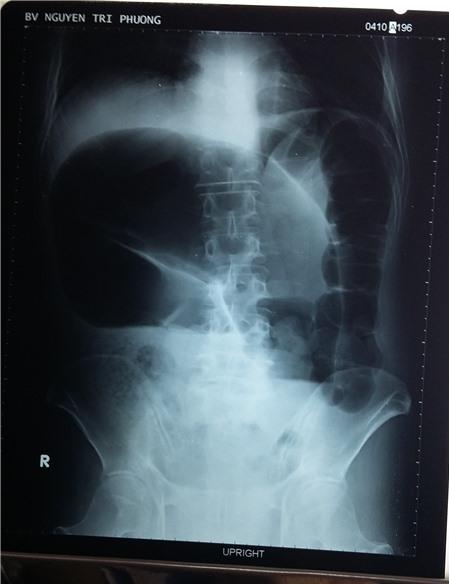

Hình X-quang cho thấy đoạn ruột phía trên bị dãn to do xoắn ruột (Ảnh: TNLP)

bị tắc ruột, các bác sĩ BV Nguyễn Tri Phương cho bệnh nhân chụp X-quang, CT bụng và xác định bệnh nhân bị “Xoắn đại tràng

sigma” làm bít tắt ruột già

và đoạn ruột phía trên bị dãn to.